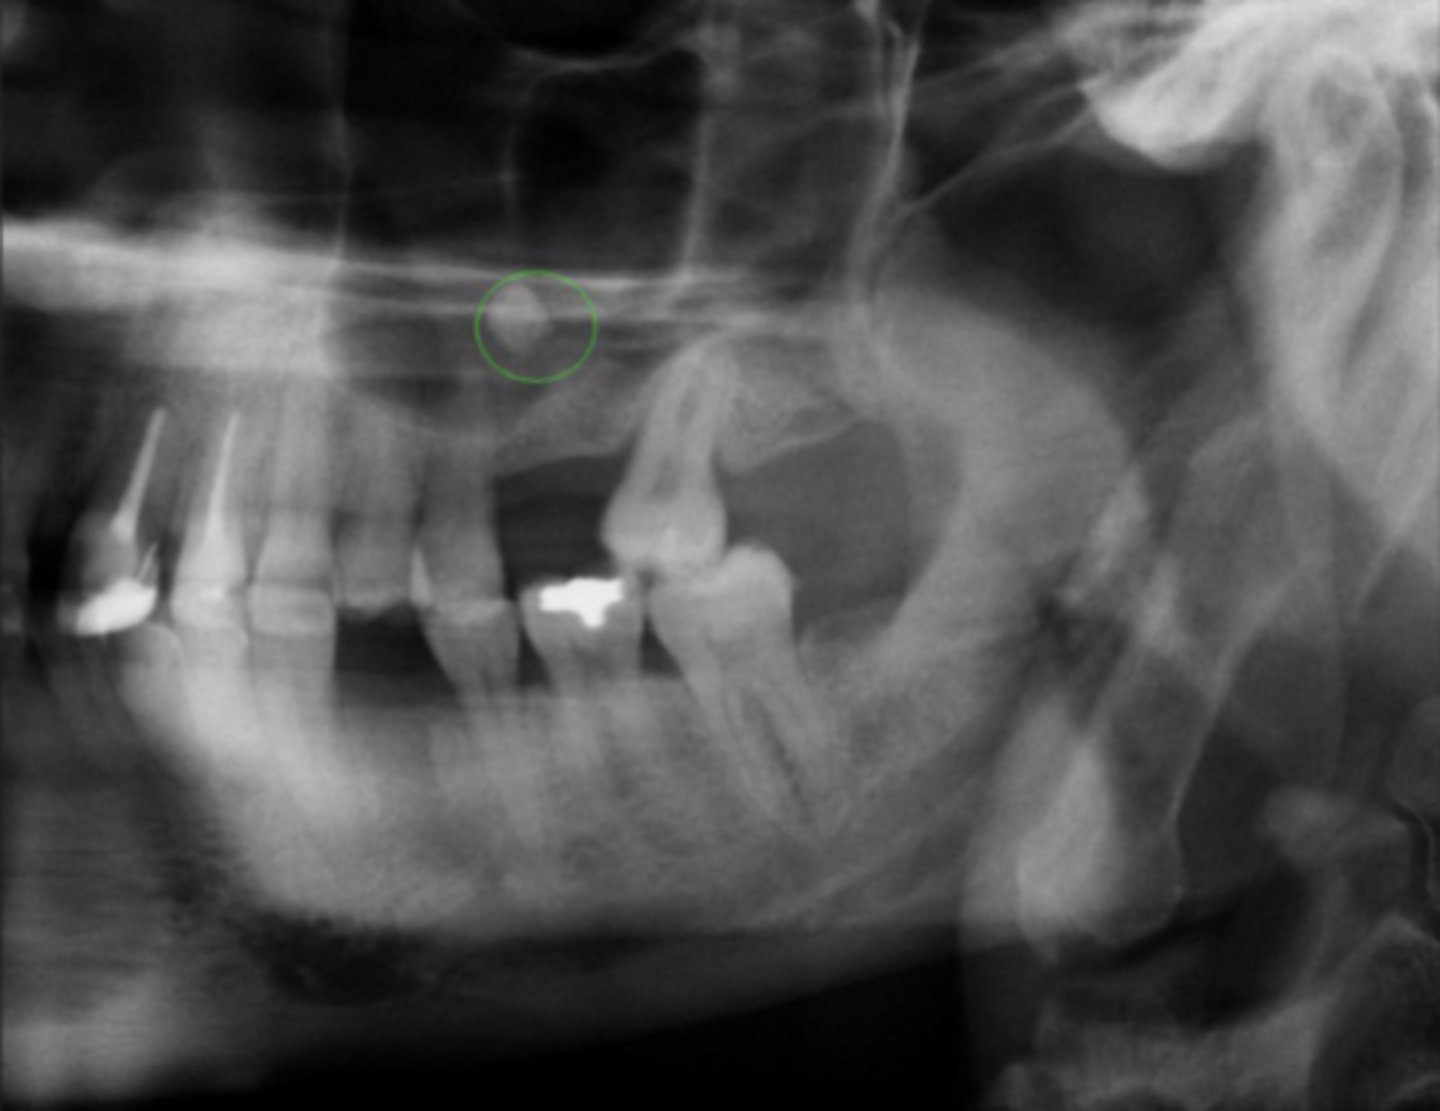

What are tonsiloliths?

Tonsil Stones: calcified masses of debris in tonsillar crypts

How do tonsiloliths appear radiographically?

Multiple small radiopacities superimposed over mandibular ramus, can be uni or bilateral

What are sialoliths?

Salivary Stones: calcified stones within salivary ducts

Which salivary gland most commonly develops sialoliths?

Submandibular gland (>80%)